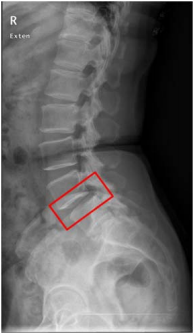

33 如圖所示,54 歲女性常感腰酸痛,自訴無外傷史,不能久站,最適當的診斷為何? (A)椎間盤突出症(HIVD) (B)脊椎解離(Spondylolysis) (C)腰椎椎管狹窄症(Lumbar spinal stenosis) (D)脊椎滑脫(Spondylolisthesis)